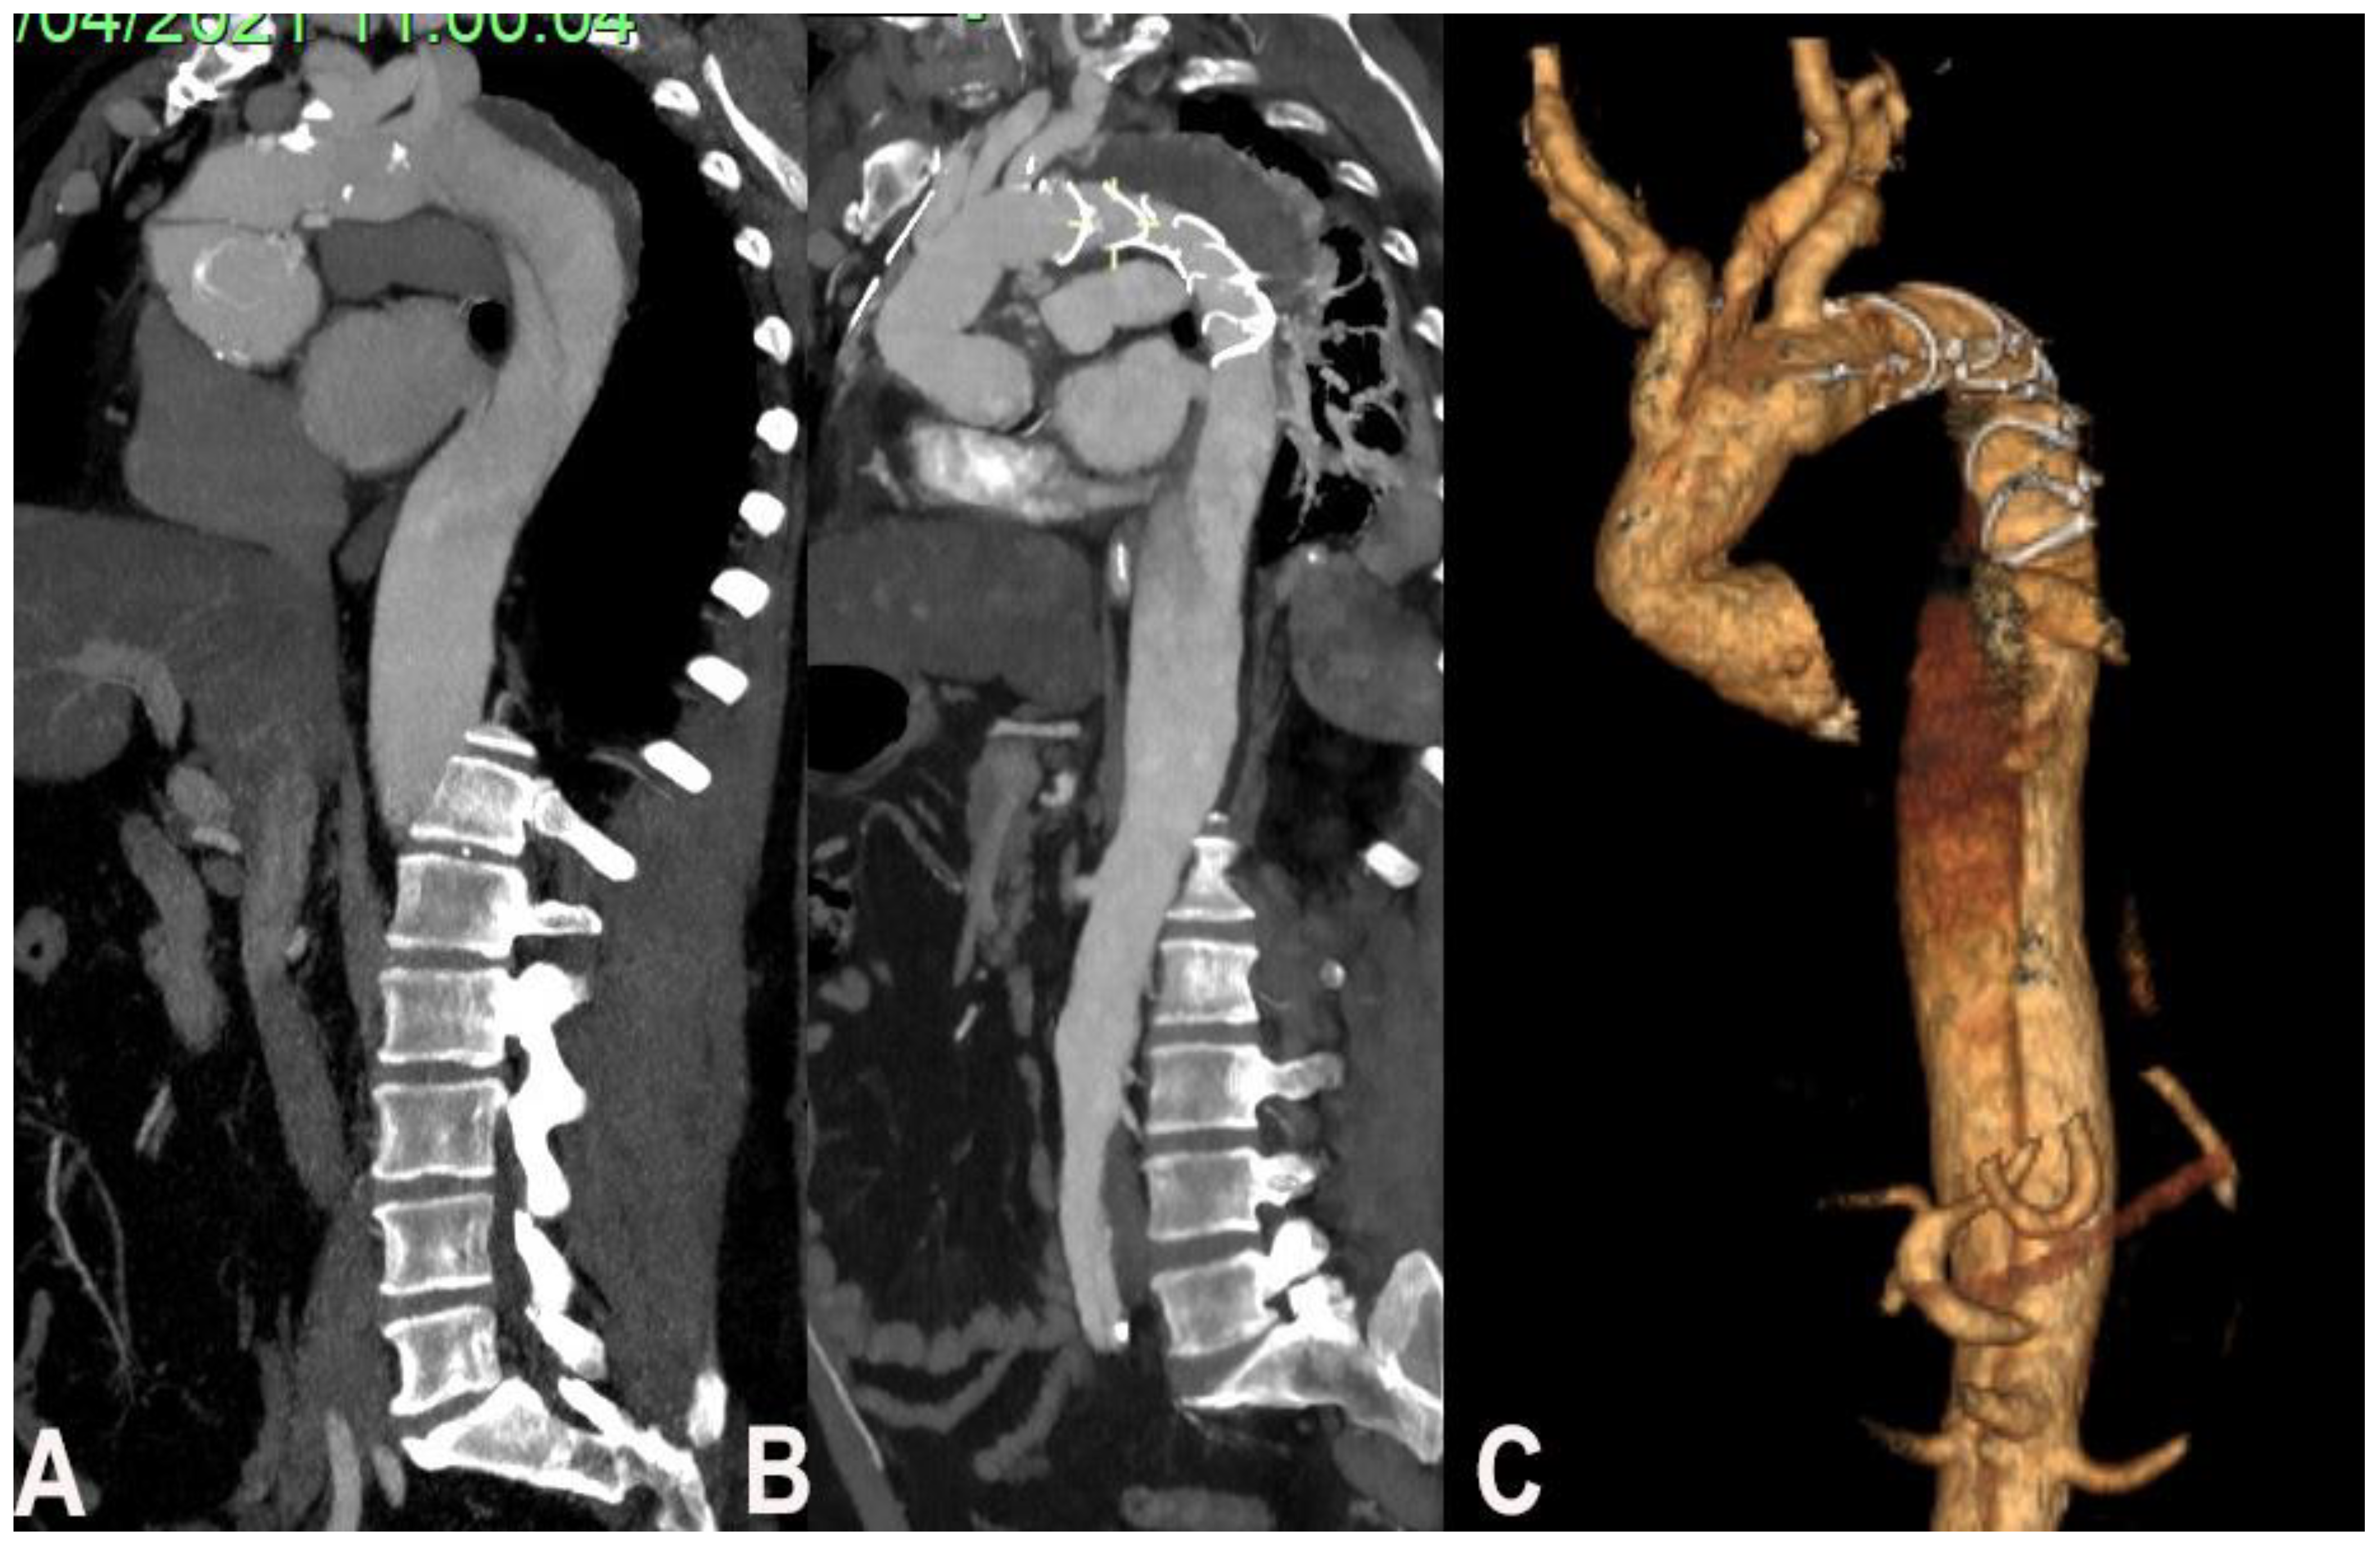

3.2. Chronic Aortic Dissection

Residual aortic dissection represents the most frequent indication for the use of the frozen elephant trunk [8].

The possibility to use FET depends on entry tear position and involvement of the thoraco-abdominal aorta including visceral branches. The study of visceral branches should be accurately evaluated, because a selective origin from the false lumen represent a contraindication to FET since the high risk of FL thrombosis and hence malperfusion (Figure 1).

Figure 1. (A). Chronic residual aortic dissection, (B) post-operative CT scan, (C) post-operative CT scan reconstruction.